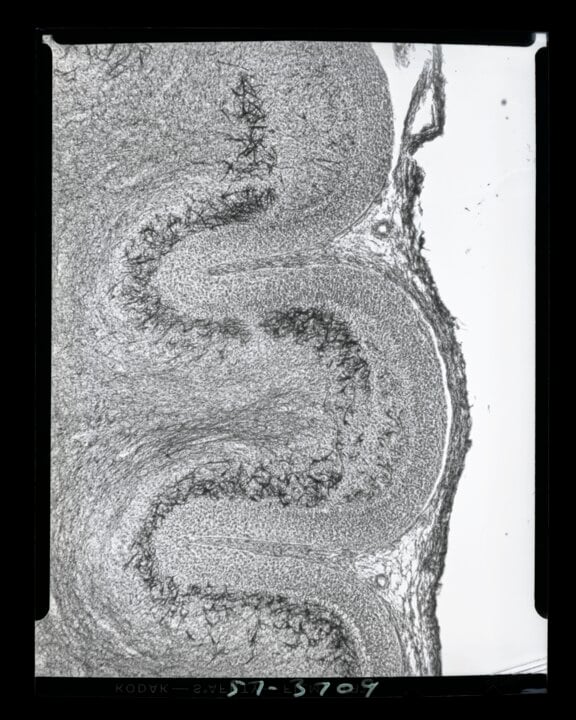

2 (of 2) Image four in a photomicroscopy series of chick embryo cerebellum and optical cortex development, dating from May 1957. These images document some of Levi-Montalcini's work studying the generation of chick optic nerves.

Photo: © Becker Medical Library, Washington University School of Medicine

1 (of 2) Image 15 in a photomicroscopy series of chick embryo cerebellum and optical cortex development, dating from May 1957. These images document some of Levi-Montalcini's work studying the generation of chick optic nerves.

© Becker Medical Library, Washington University School of Medicine

2 (of 2) Image three in a photomicroscopy series of chick embryo cerebellum and optical cortex development, dating from May 1957. These images document some of Levi-Montalcini's work studying the generation of chick optic nerves.